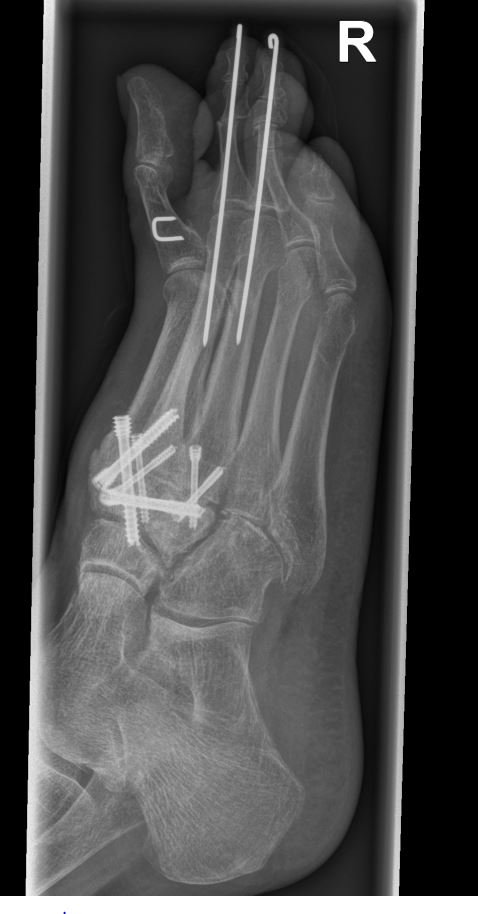

Es gibt neben der Möglichkeit mit der in situ TMT II, III Arthrodese auch die Möglichkeit Fehlstellungen wie den Pes metatarsus adductus zu adressieren (Abb. 9 und Abb. 24 zeigen das prä- und postoperative Röntgenbild eines Patienten mit Pes adductus Korrektur).

Zum Lesen der Bildbeschreibung und zur Vollansicht bitte die Bilder anklicken. Bilder: C. Hase.

• Röntgenkontrolle nach 8-10 Wochen, dann - je nach knöchernem Durchbau - Übergang zur Vollbelastung im Konfektionsschuh (Abb. 24 und 25).